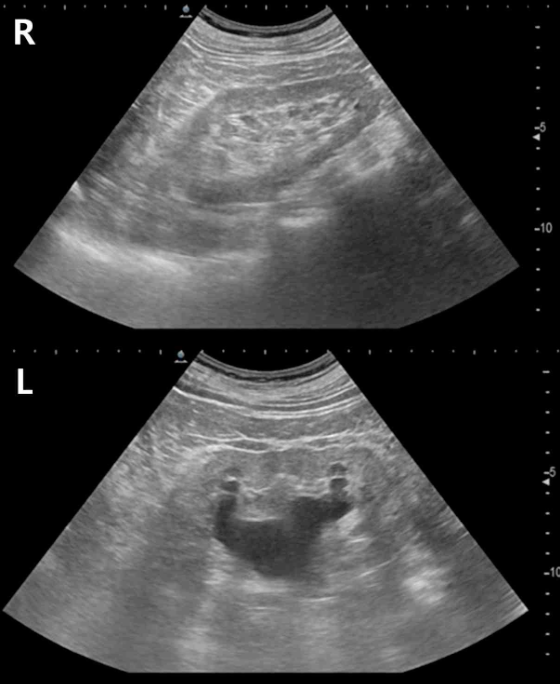

55세 여자가 3일 전부터 왼쪽 옆구리가 불편하고 소변이 잘 나오지 않는다며 병원에 왔다. 3년 전 자궁경부암으로 자궁 적출술과 방사선치료를 받았다. 혈압 130/80 mmHg, 맥박 108회/분, 호흡 20/분, 체온 36.7°C이다. 검사 결과는 다음과 같다. 신장 초음파 사진이다. 치료는?

U/S: Hydronephrosis on Lt. kidney

자궁적출술, RTx 과거력이 있는 환자에서 일측성 hydronephosis가 나타나므로 요관 폐색 의심 하에 nephrostomy를 시행하여 배액한다.

콩팥 초음파에서 hydronephrosis 소견이 있는데, 일측성이므로 bladder neck 위쪽 level의 상부 요로폐색으로 진단할 수 있다. 만약 하부 요로폐색이었다면 hydronephrosis가 bilateral하게 나타났을 가능성이 높다.